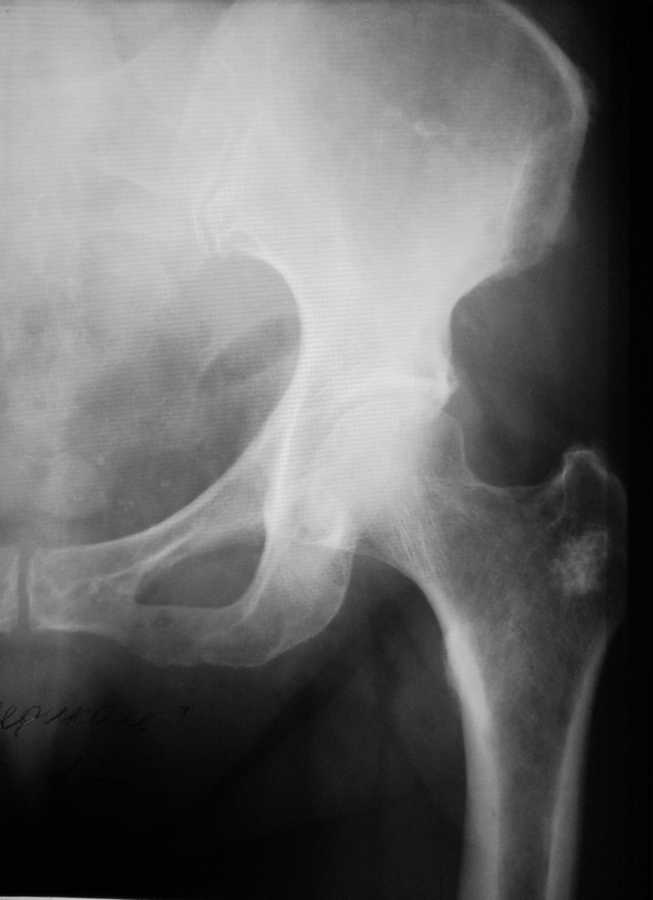

Уважаемые коллеги! Прошу Вас помощи по поводу ситуации, представленной на снимке левого Т/Б сустава. Пациентка 65 лет, рост около 165, вес около 90кг.Клинически боли в суставе при ходьбе.При пальпации болезненность в области вертела. Пассивные движения в суставе в полном объеме, безболезненны.

1. Это рентгенконтрастное новообразование (далее НО), ок.1.5-2 см, которое поразило большой вертел бедра женщины 65-ти лет, рост... вес... и через это она (женщина) испытывает боли при ходьбе и когда ей вертел пальпируют.

2. Жалобы с суставом не связаны.

4. По снимку не совсем ясно, есть ли зона лизиса вокруг НО? а следом за ней нет ли ободка склероза? Нет ли изменений в кортикале, истончение, прорыв, периостальных реакций?

Желательно сделать КТ, конечно.

Практический совет: если есть НО, и Вы решили, что боли у пациентки связаны именно с ним, нужно резать. В данном конкретном случае НО небольшое, вы спокойно делаете эксцизию, заполняете пострезекционный дефект, а материал отдаете морфологу на исследование. И он, с высокой точностью, удовлетворит наше любопытство:-)))